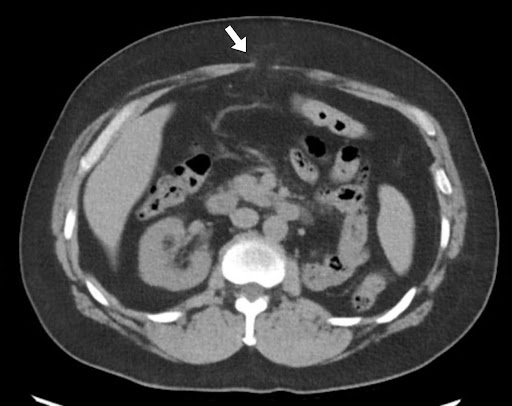

पेट और श्रोणि के गैर-विपरीत बढ़ाया सीटी ने अक्षीय इमेजिंग पर दो वसा युक्त मिडलाइन हर्निया दोषों का प्रदर्शन किया। यूरोपीय हर्निया सोसाइटी (ईएचएस) वर्गीकरण के अनुसार, ये एक एम 2 हर्निया के अनुरूप हैं जो चौड़ाई में 16 मिमी और क्रानियोकौडल लंबाई में 8 मिमी मापते हैं, और एक एम 3 हर्निया की चौड़ाई 37 मिमी और लंबाई में 30 मिमी है। धनु पुनर्निर्माण ने अतिरिक्त फेशियल दोषों के साथ-साथ पूर्व मिडलाइन चीरा के साथ क्षीण प्रावरणी के क्षेत्रों का खुलासा किया, जो सबक्लिनिकल हर्निया के अनुरूप था।

चित्रा 1 अक्षीय छवियों पर वसा युक्त एम 2 और एम 3 हर्निया को दिखाता है। धनु विचार पैथोलॉजी का अधिक व्यापक चित्रण प्रदान करते हैं, M1-M3 क्षेत्रों में फैले क्षीण प्रावरणी का प्रदर्शन करते हैं, अतिरिक्त इंटरपेरिटल हर्निया दोषों (धराशायी तीर) का विचारोत्तेजक फेशियल उतार-चढ़ाव, और M2 ज़ोन (तीर) से बेहतर एक छोटा हर्निया दोष जो अक्षीय इमेजिंग पर स्पष्ट नहीं था।

चित्रा 1. अक्षीय और धनु विचारों के साथ सीटी पेट और श्रोणि। सीटी इमेजिंग मिडलाइन वसा युक्त हर्निया दोषों का प्रदर्शन करती है।